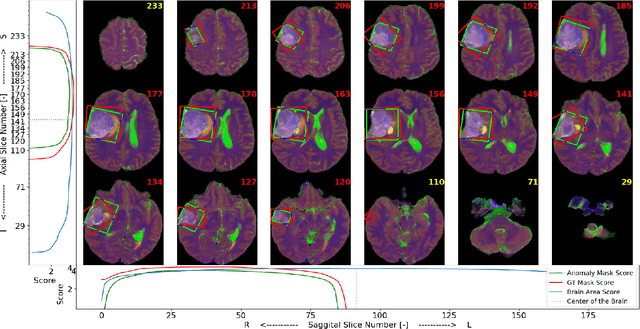

Abstract:In clinical practice, we often see significant delays between MRI scans and the diagnosis made by radiologists, even for severe cases. In some cases, this may be caused by the lack of additional information and clues, so even the severe cases need to wait in the queue for diagnosis. This can be avoided if there is an automatic software tool, which would supplement additional information, alerting radiologists that the particular patient may be a severe case. We are presenting an automatic brain MRI Screening Tool and we are demonstrating its capabilities for detecting tumor-like pathologies. It is the first version on the path toward a robust multi-pathology screening solution. The tool supports Federated Learning, so multiple institutions may contribute to the model without disclosing their private data.